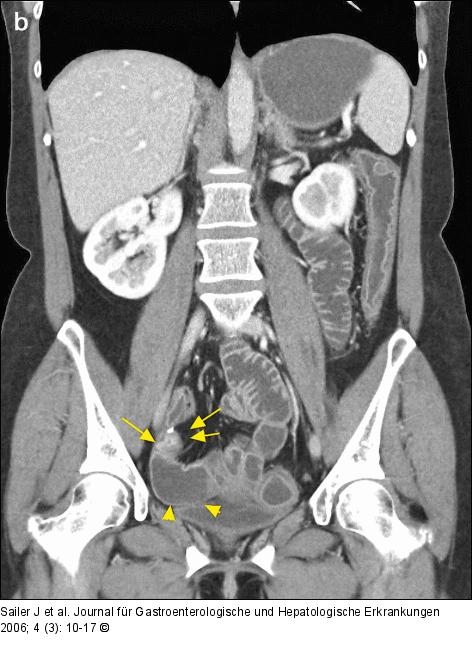

Abbildung 4a-b: Morbus Crohn-Rezidiv Morbus Crohn-Rezidiv im neoterminalen Ileum nach Ileocoecalresektion. CT-Enteroklysma eines 38jährigen Patienten zeigt an der Anastomose eine höhergradige kurzstreckige Stenose mit Wandverdickung und verstärkter Kontrastmittelaufnahme (Pfeile), begleitende prästenotische Dilatation (Pfeilspitzen). |

Morbus Crohn-Rezidiv im neoterminalen Ileum nach Ileocoecalresektion. CT-Enteroklysma eines 38jährigen Patienten zeigt an der Anastomose eine höhergradige kurzstreckige Stenose mit Wandverdickung und verstärkter Kontrastmittelaufnahme (Pfeile), begleitende prästenotische Dilatation (Pfeilspitzen). |